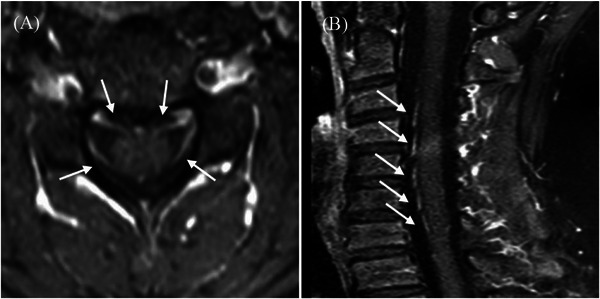

Results: Of the 34 patients, six (17.6%) were tested positive for anti-NF155 antibodies. The cohort was male-dominated (male-to-female ratio of 4:2) with symptoms starting primarily in school-aged children. The symptoms included progressive limb weakness, sensory ataxia, and tremors. Notably, cerebrospinal fluid (CSF) protein levels were significantly elevated in seropositive patients. Electrophysiological studies indicated sensorimotor polyneuropathy, and neuroimaging revealed nerve root thickening. While intravenous immunoglobulin (IVIG) therapy was not effective, a combination of glucocorticoids, rituximab, and plasma exchange showed promise. At the final follow-up, all patients experienced symptom relief and could perform daily activities without relapse.